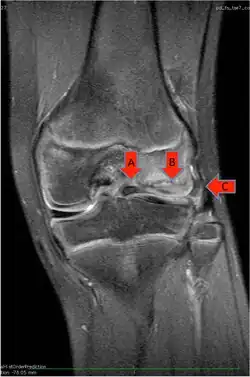

Klinisch auffällige Scheibenmenisken, die Beschwerden oder ein störendes Schnappen erzeugen oder sogar aufgrund von inneren Zerreißungen des Gewebes oder bei kompletten Rissen der Menisken Schmerzen erzeugen und den Gelenkknorpel schädigen, müssen operativ angegangen werden. Das Ziel der Operation ist neben der Beseitigung der subjektiven Beschwerden wie Schmerzen, Schnapp-Phänomene und Funktionsstörungen die Vermeidung von weiteren Gelenkschäden und Meniskuseinrissen. Ein Aufschieben der Operation, wenn eine Indikation dazu besteht, erhöht das Risiko von Gelenkschäden nachhaltig. Bei der Operation wird im Rahmen einer Arthroskopie der Scheibenmeniskus von seiner zentralen Öffnung (an der Eminentia intercondylaris) eingeschnitten und dann teilentfernt (s.Abbildungen). Die Teilresektion ist beim Scheibenmeniskus nicht einfach: Einerseits ist der seitliche Gelenkspalt, in dem sich typischerweise der Scheibenmeniskus befindet, schon natürlicherweise sehr eng. Andererseits lässt sich der seitliche Gelenkspalt nicht durch einen „Release“ des Außenbandes (gezielte Teilzerreißung des Seitenbandes) erweitern, wie das beim Innenband bei operativen Schwierigkeiten standardmäßig durch sogenanntes Needling durchgeführt werden kann. Der seitliche Gelenkspalt ist darüber hinaus durch den dicken Scheibenmeniskus selbst ausgefüllt (s. Abb.). Die Arbeit mit mechanischen Operationsinstrumenten ist in dem schmalen Gelenkspalt bei Kindern technisch anspruchsvoll. Daher werden oft für die Teilentfernung der Menisken neben den entsprechenden Handinstrumenten (Punch) meist motorische Instrumente („Shaver“), oder Laser-Instrumente bzw. elektrische sogenannte Ablatoren verwendet. Möglicherweise haben die HF-Geräte (Hochfrequenz-Geräte) und die Laser aber tiefer schädigende Auswirkungen auf das verbleibende Meniskusgewebe, weshalb die Verwendung der HF-Geräte und besonders von Laser eher zurückhaltend erfolgen sollte. Einige Kliniken verwenden aus diesen Gründen statt der arthroskopischen Technik inzwischen wieder offene Zugänge zum Scheibenmeniskus. Entscheidend für die Wahl des Operationsverfahrens ist die zuverlässige Übersicht im Gelenk und die Erfahrung des Operateurs mit dem jeweiligen Verfahren.

Besonders aufwändig ist die operative Therapie eines zerrissenen und/oder luxierten kompletten Scheibenmeniskus. Zunächst muss dieser Zustand erkannt werden. Denn im MRT kann möglicherweise nur ein komplexer Meniskusriss dargestellt sein. Der Verdacht ergibt sich vor allem aus dem jungen Lebensalter der jeweiligen Patienten. Liegen harte Anhaltspunkte für einen Scheibenmeniskus vor, muss zunächst die Reposition und Ausbreitung des im vorderen Recessus liegenden Meniskus auf die Tibiagelenkfläche erfolgen, anschließend die Teilresektion des zentralen Meniskusteils und anschließend die Refixierung des Hinterhorns und der Pars intermedia an der Kapsel. Wichtig ist, den Hiatus popliteus, den Durchtrittspunkt der Popliteussehne durch die Meniskusbasis, hierbei nicht durch die Meniskusnaht zu verschließen.

Die Teilresektion muss sparsam nur bis zu dem Punkt durchgeführt werden, an dem die Oberschenkelrolle mit ihrer Hauptbelastungszone die Gelenkoberfläche des Schienbeinkopfplateaus erreicht. Eine Resektion über diesen Punkt hinaus sollte nicht erfolgen, da die Schutzwirkung des Meniskus für die Gelenkoberfläche sonst nicht mehr gegeben ist.